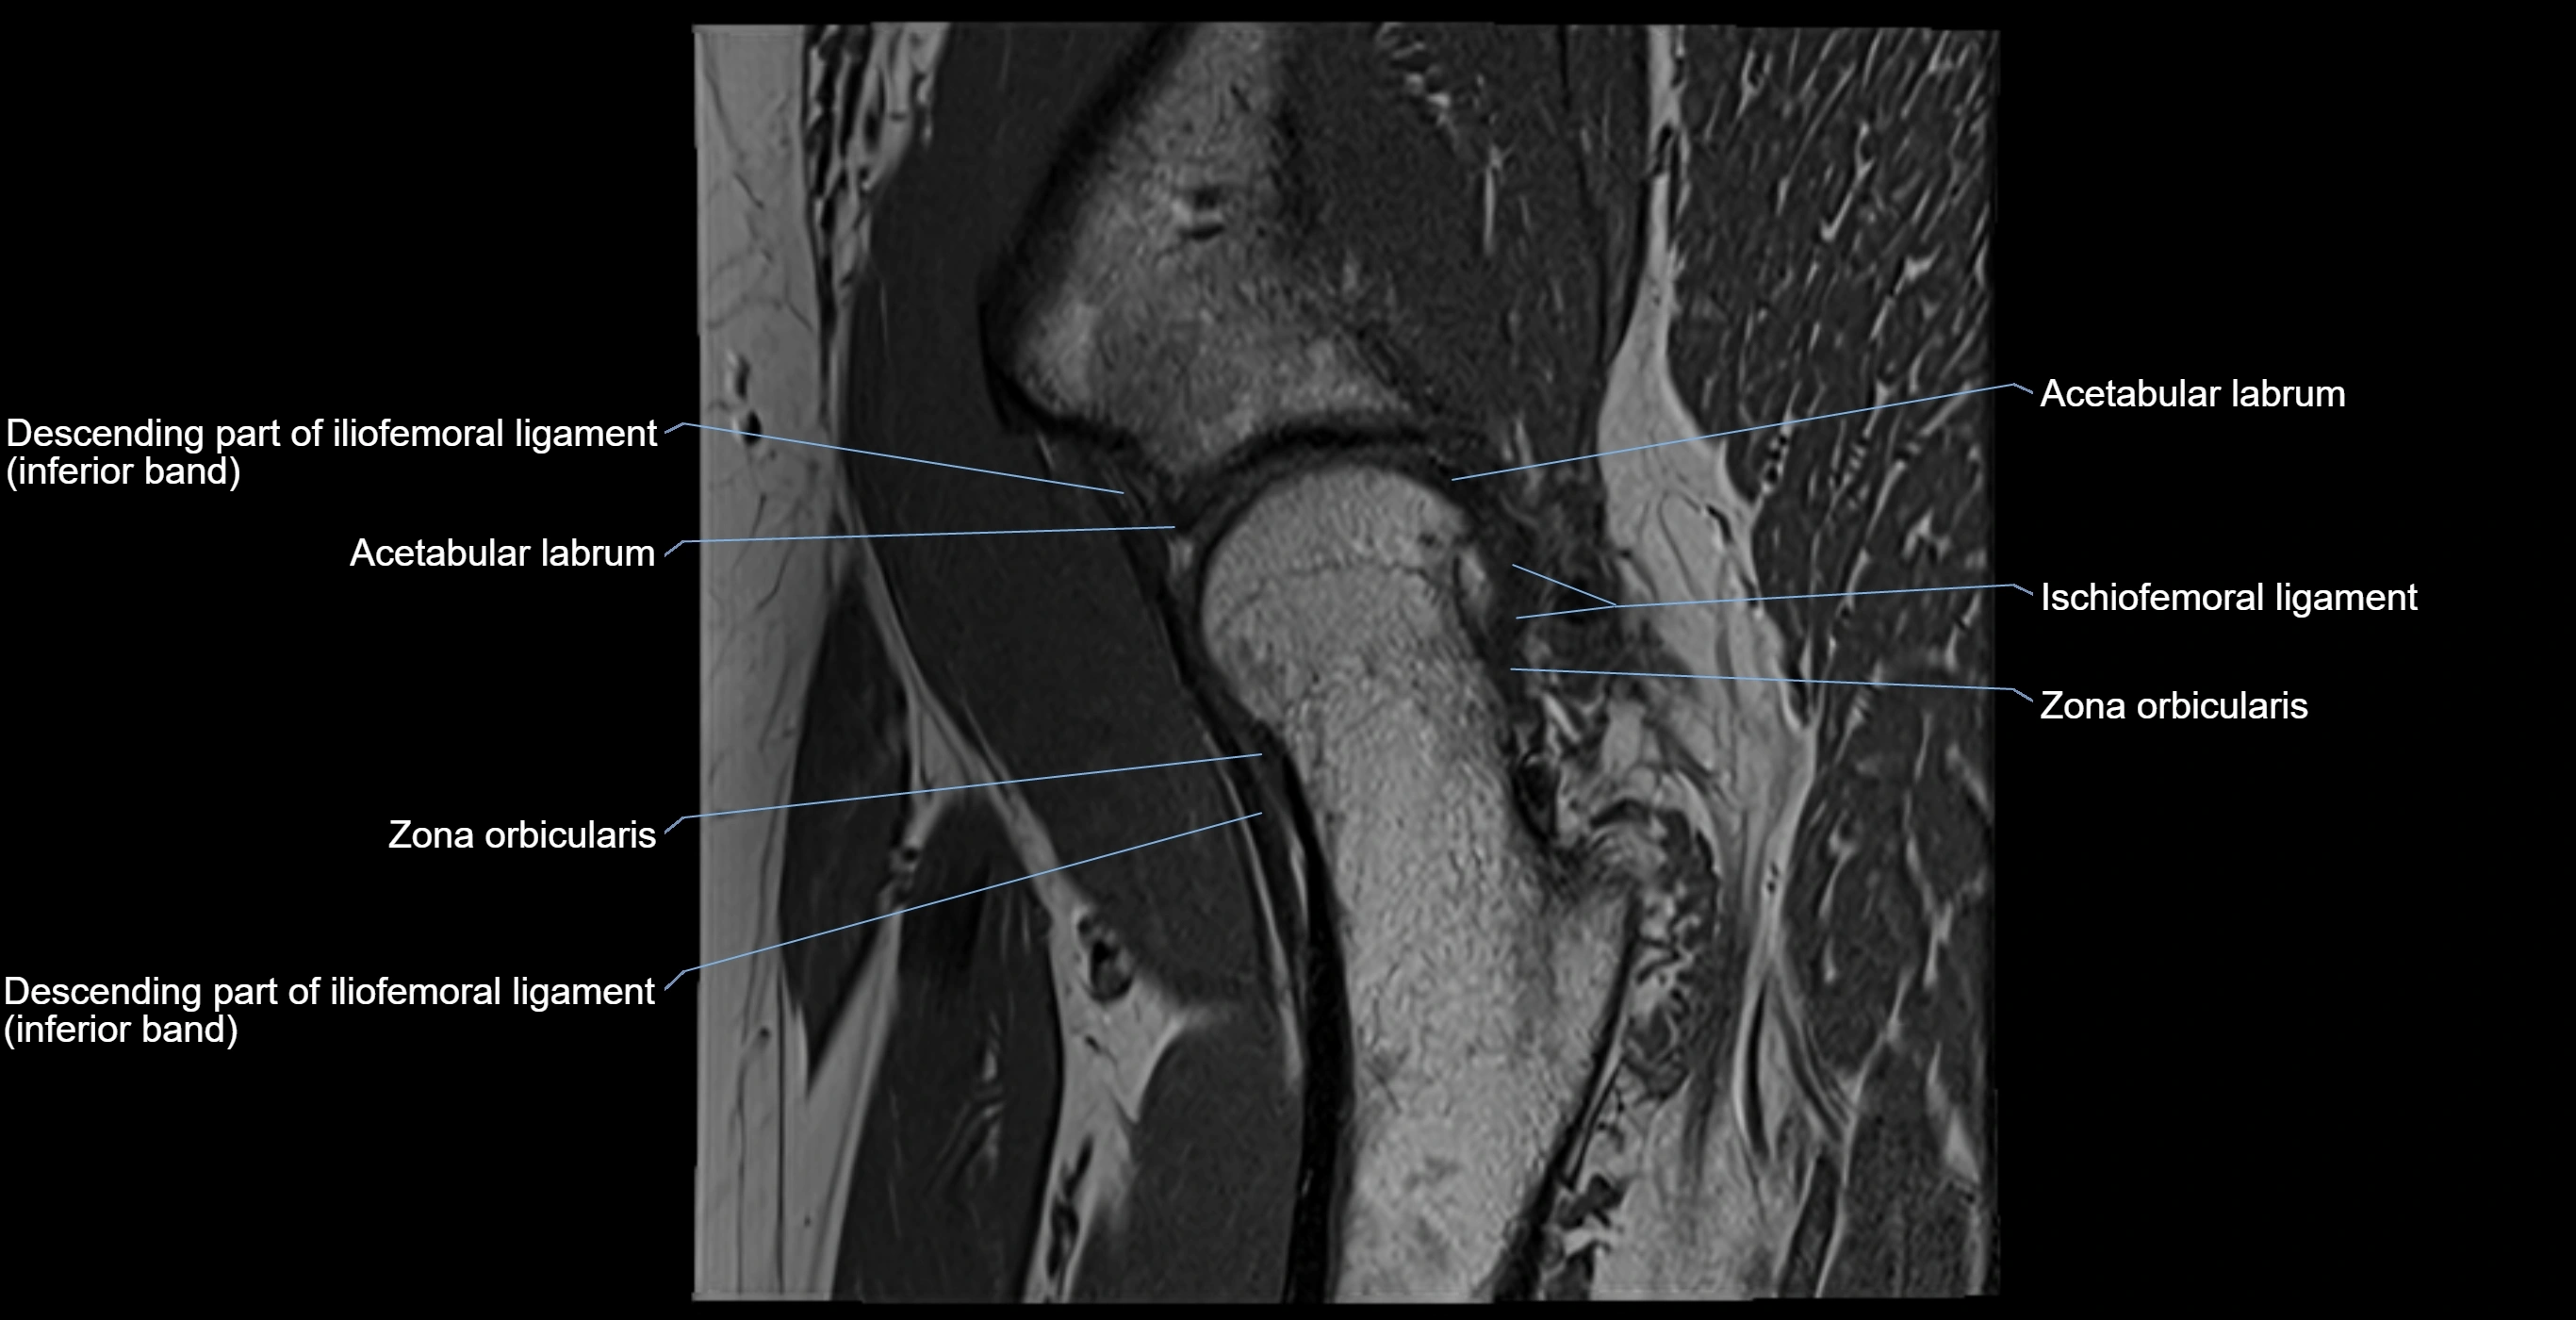

MRI Appearance

T1-weighted images:

• Labrum: low signal intensity (dark)

• Surrounded by intermediate signal joint fluid (bright on arthrogram)

• Tears: linear or focal areas of intermediate-to-high signal interrupting labral continuity

T2-weighted images:

• Joint fluid: bright, making labral tears visible as fluid extending into or around labrum

• Degeneration: may show areas of increased signal within labrum

MRI image

image